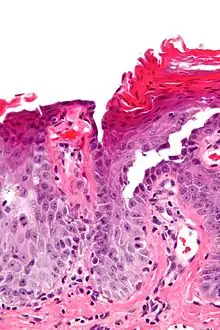

![]() صورة مجهرية للجلاد الحال للأشواك العابر, تظهر انفصال تحت القرنية وانحلال الأشواك. صورة مجهرية للجلاد الحال للأشواك العابر, تظهر انفصال تحت القرنية وانحلال الأشواك. | |